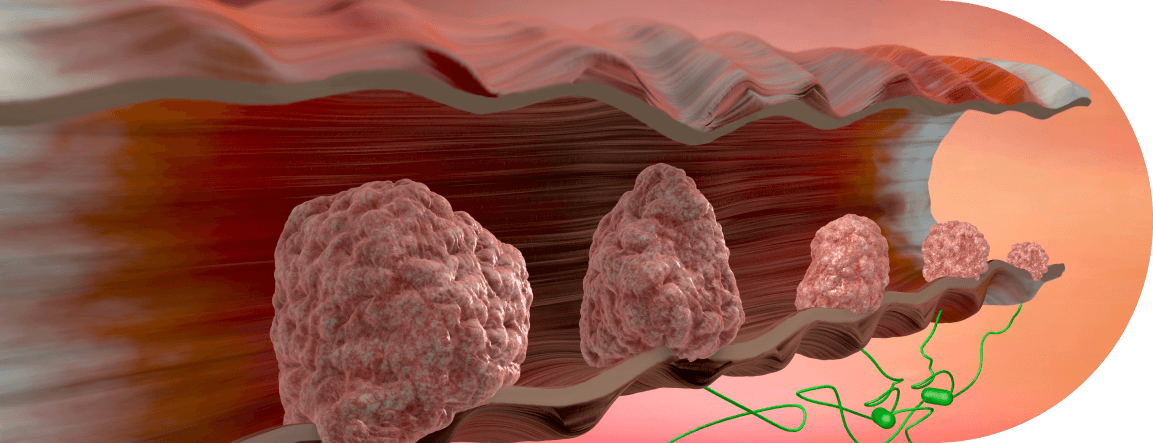

Tipos de Câncer